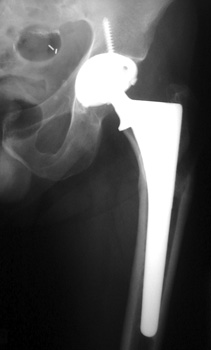

FEMORAL STEM POSITION

• Varus positioning

• Valgus positioning

Varus Normal Valgus

Varus

Valgus